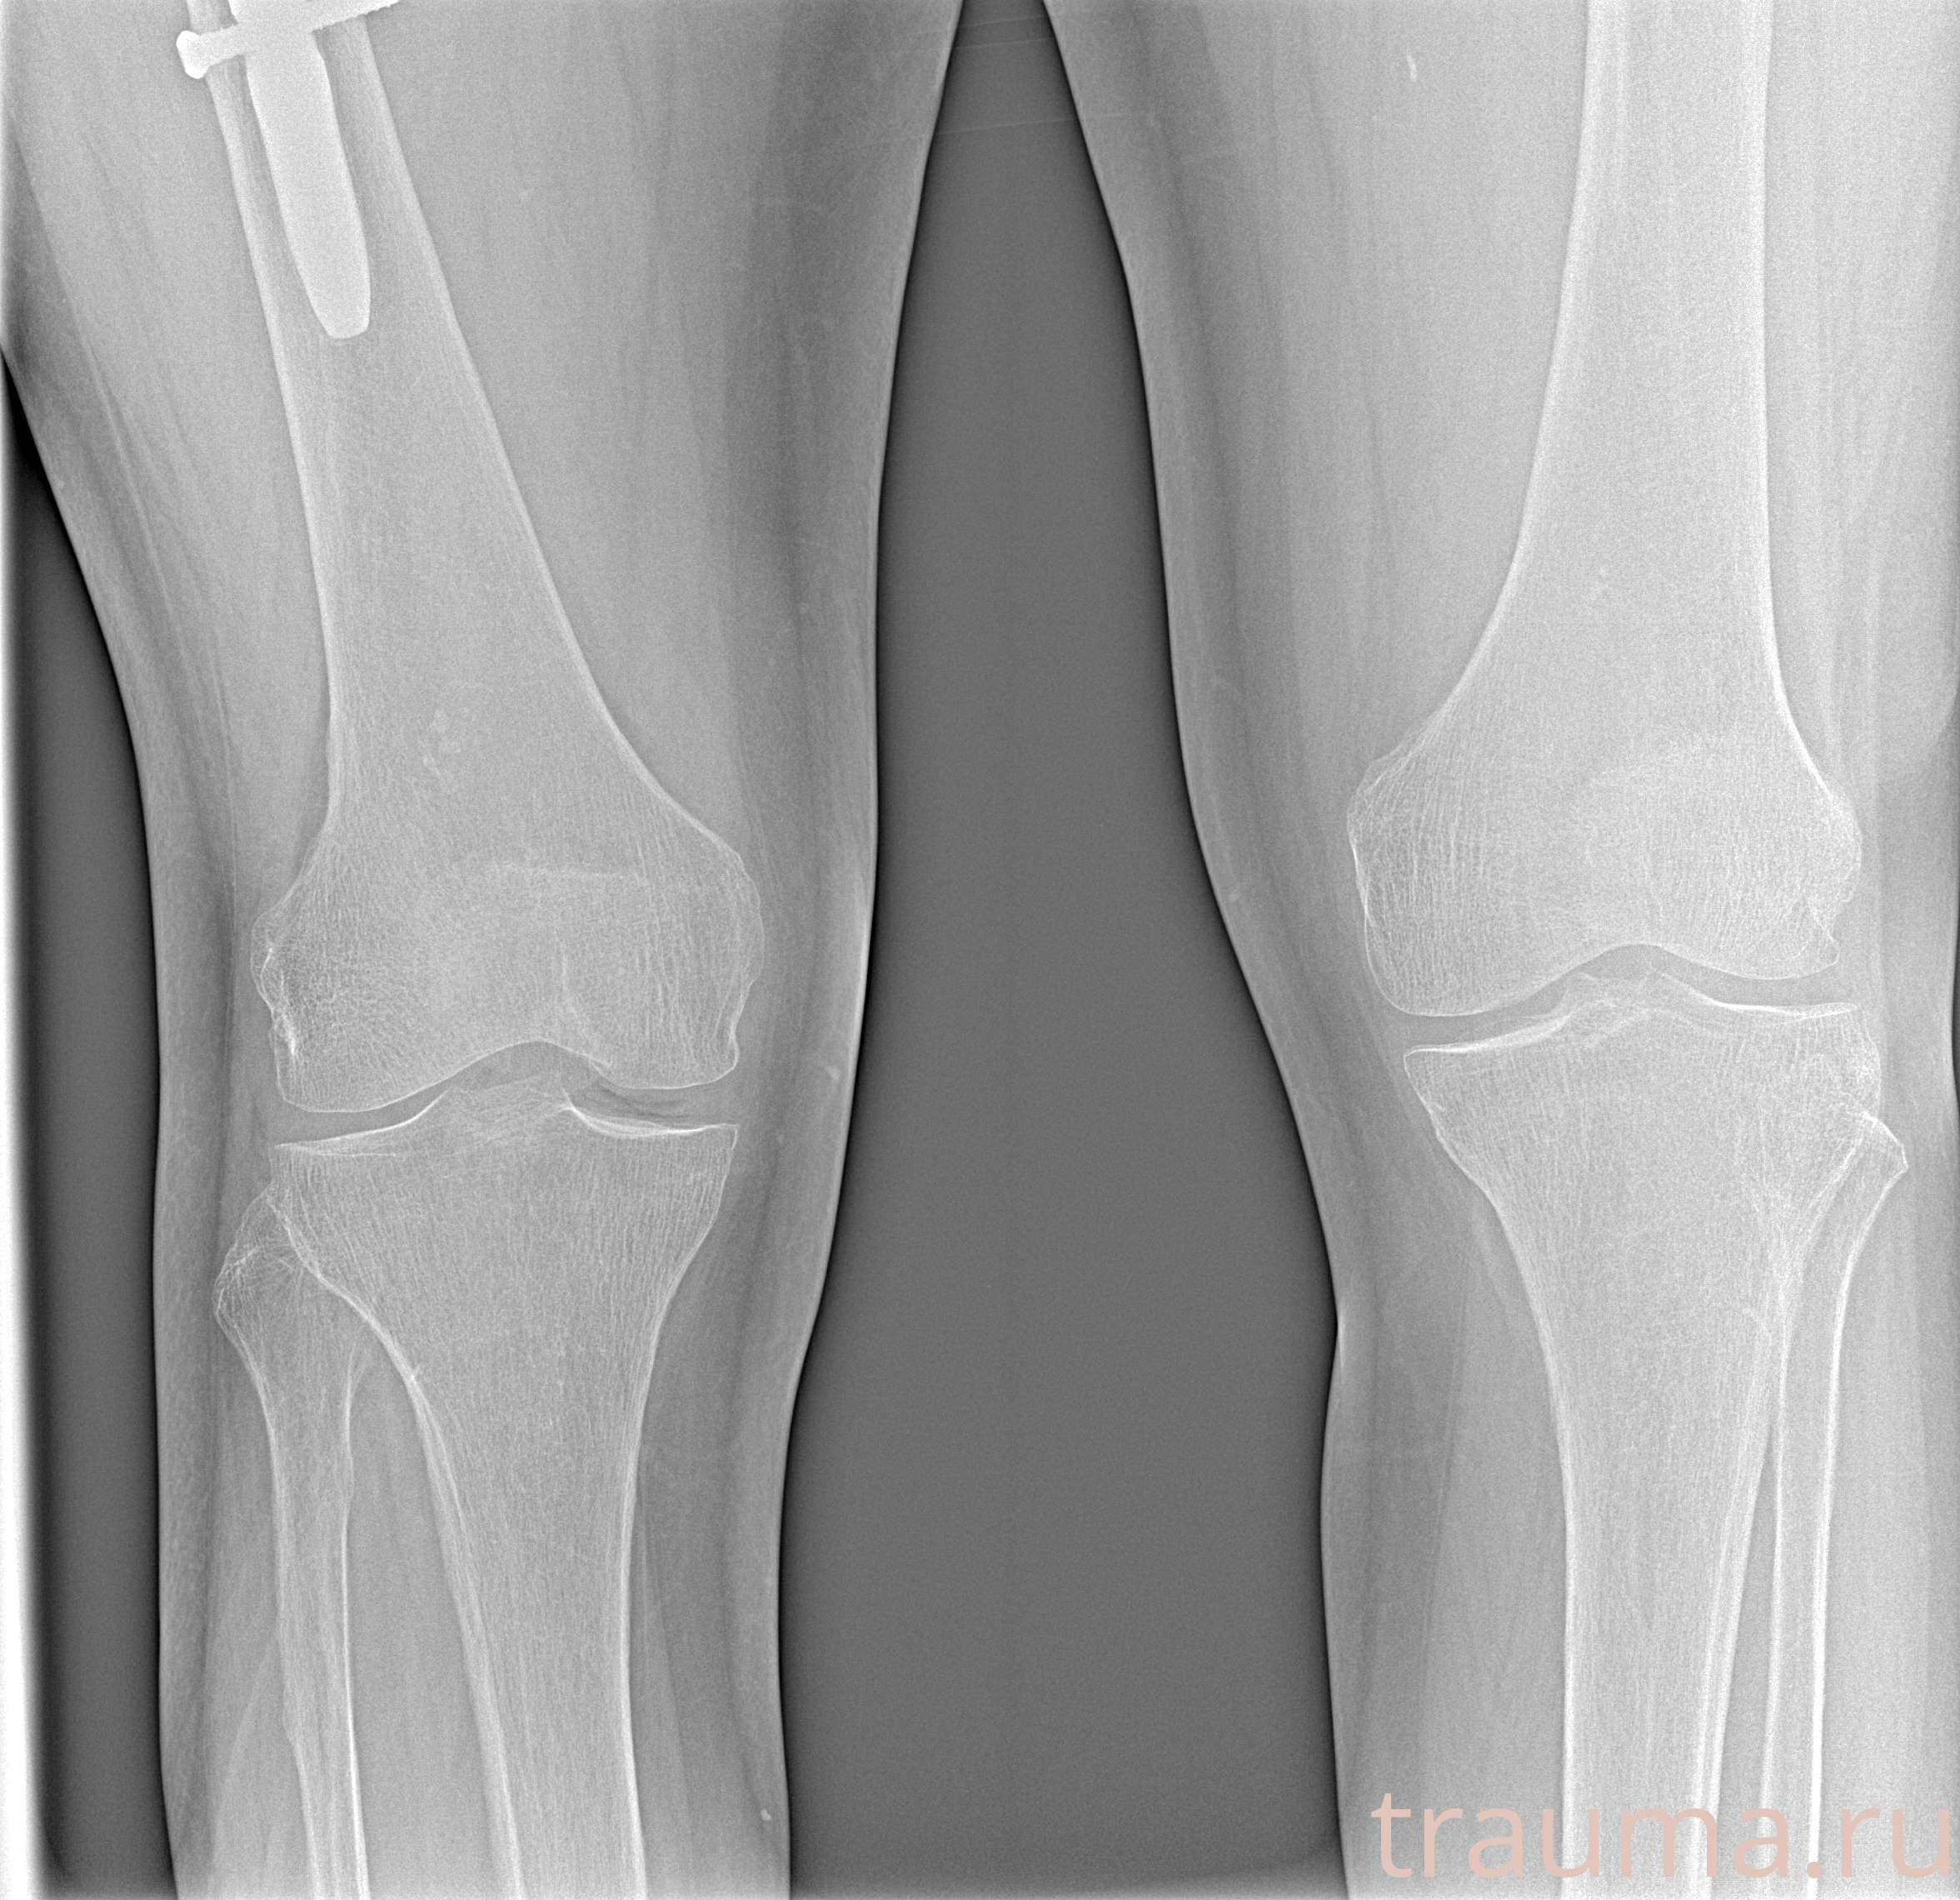

Рентгенограммы